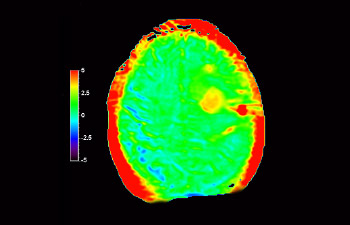

3D APT

Mayor fiabilidad diagnóstica en neurooncología